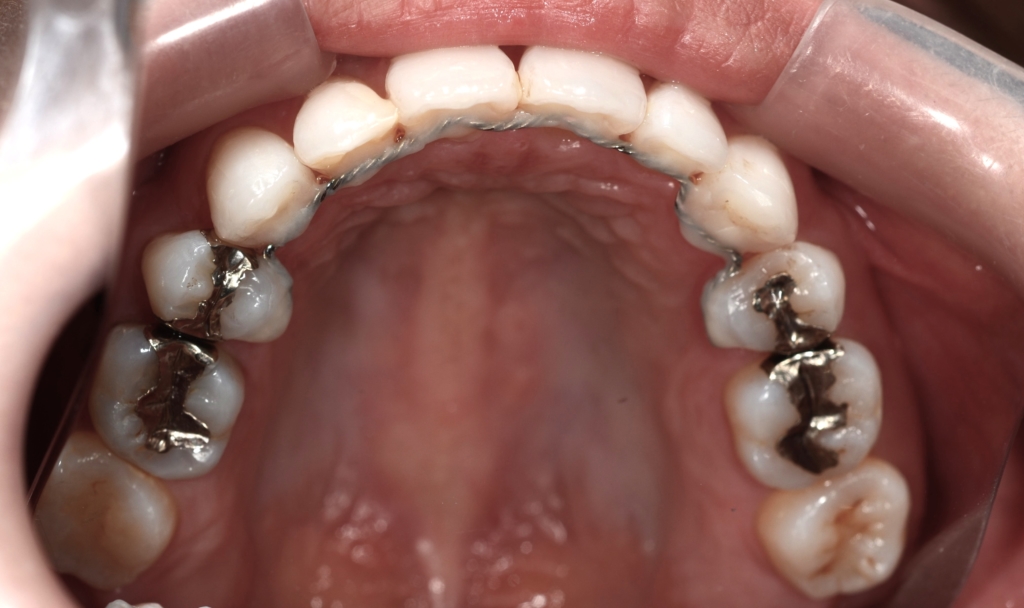

【治療装置】

マルチブラケットシステム(スタンダードtype)で矯正を開始。

上の歯列がきれいに並んで、アンカースクリューを植立する目途がついたので、上顎の口蓋正中部、臼歯部と前歯部の頬側辺りにアンカースクリューを植立しました。(計6本)

【保定】 上下ともフィックスタイプ&クリアリテーナー

・スタンダードタイプのマルチブラケットシステム

・アンカースクリューを計6本

・PLAS&パラタルバーを使用 【抜歯】

上下の左右の奥歯を1本ずつの計4本(全て第一小臼歯)を抜歯